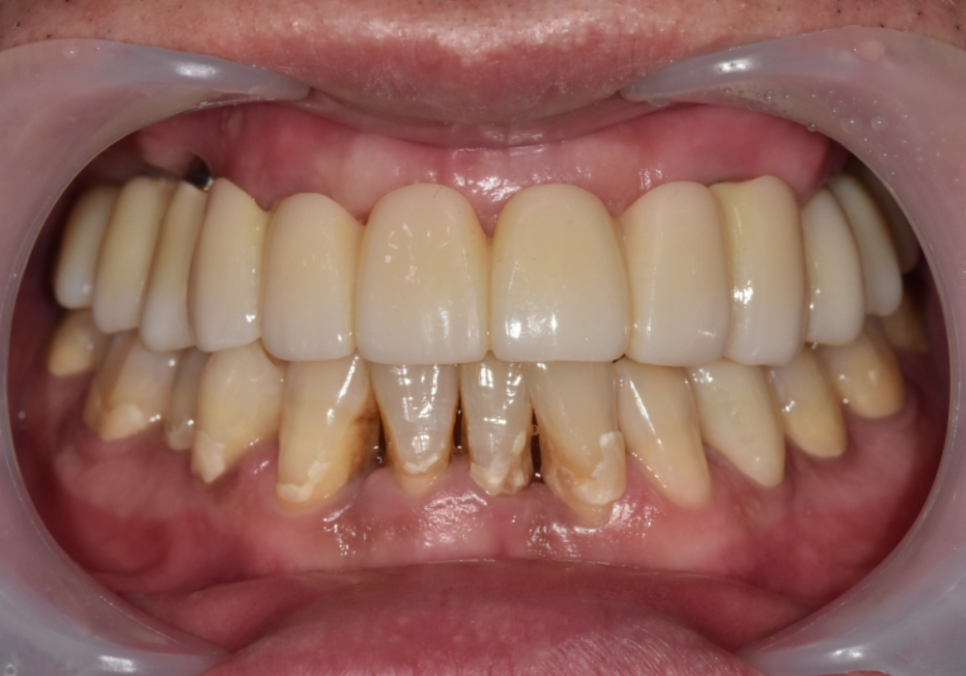

마침내 완성된 보철물을 끼워 드린 날!

기우뚱거리던 틀니를 벗어버리고,

이제는 내 치아처럼 편안하게

식사하실 수 있게 된

환자분의 모습을 보니

저도 참 뿌듯했는데요~

251111

250531(전) 251111(후)

하지만 잇몸에 얹어 쓰는 틀니와 달리,

내 뼈와 임플란트가 단단히 하나가 되는 과정은

'진짜 내 치아' 같은 힘을 얻기 위해

반드시 거쳐야 하는 시간입니다.